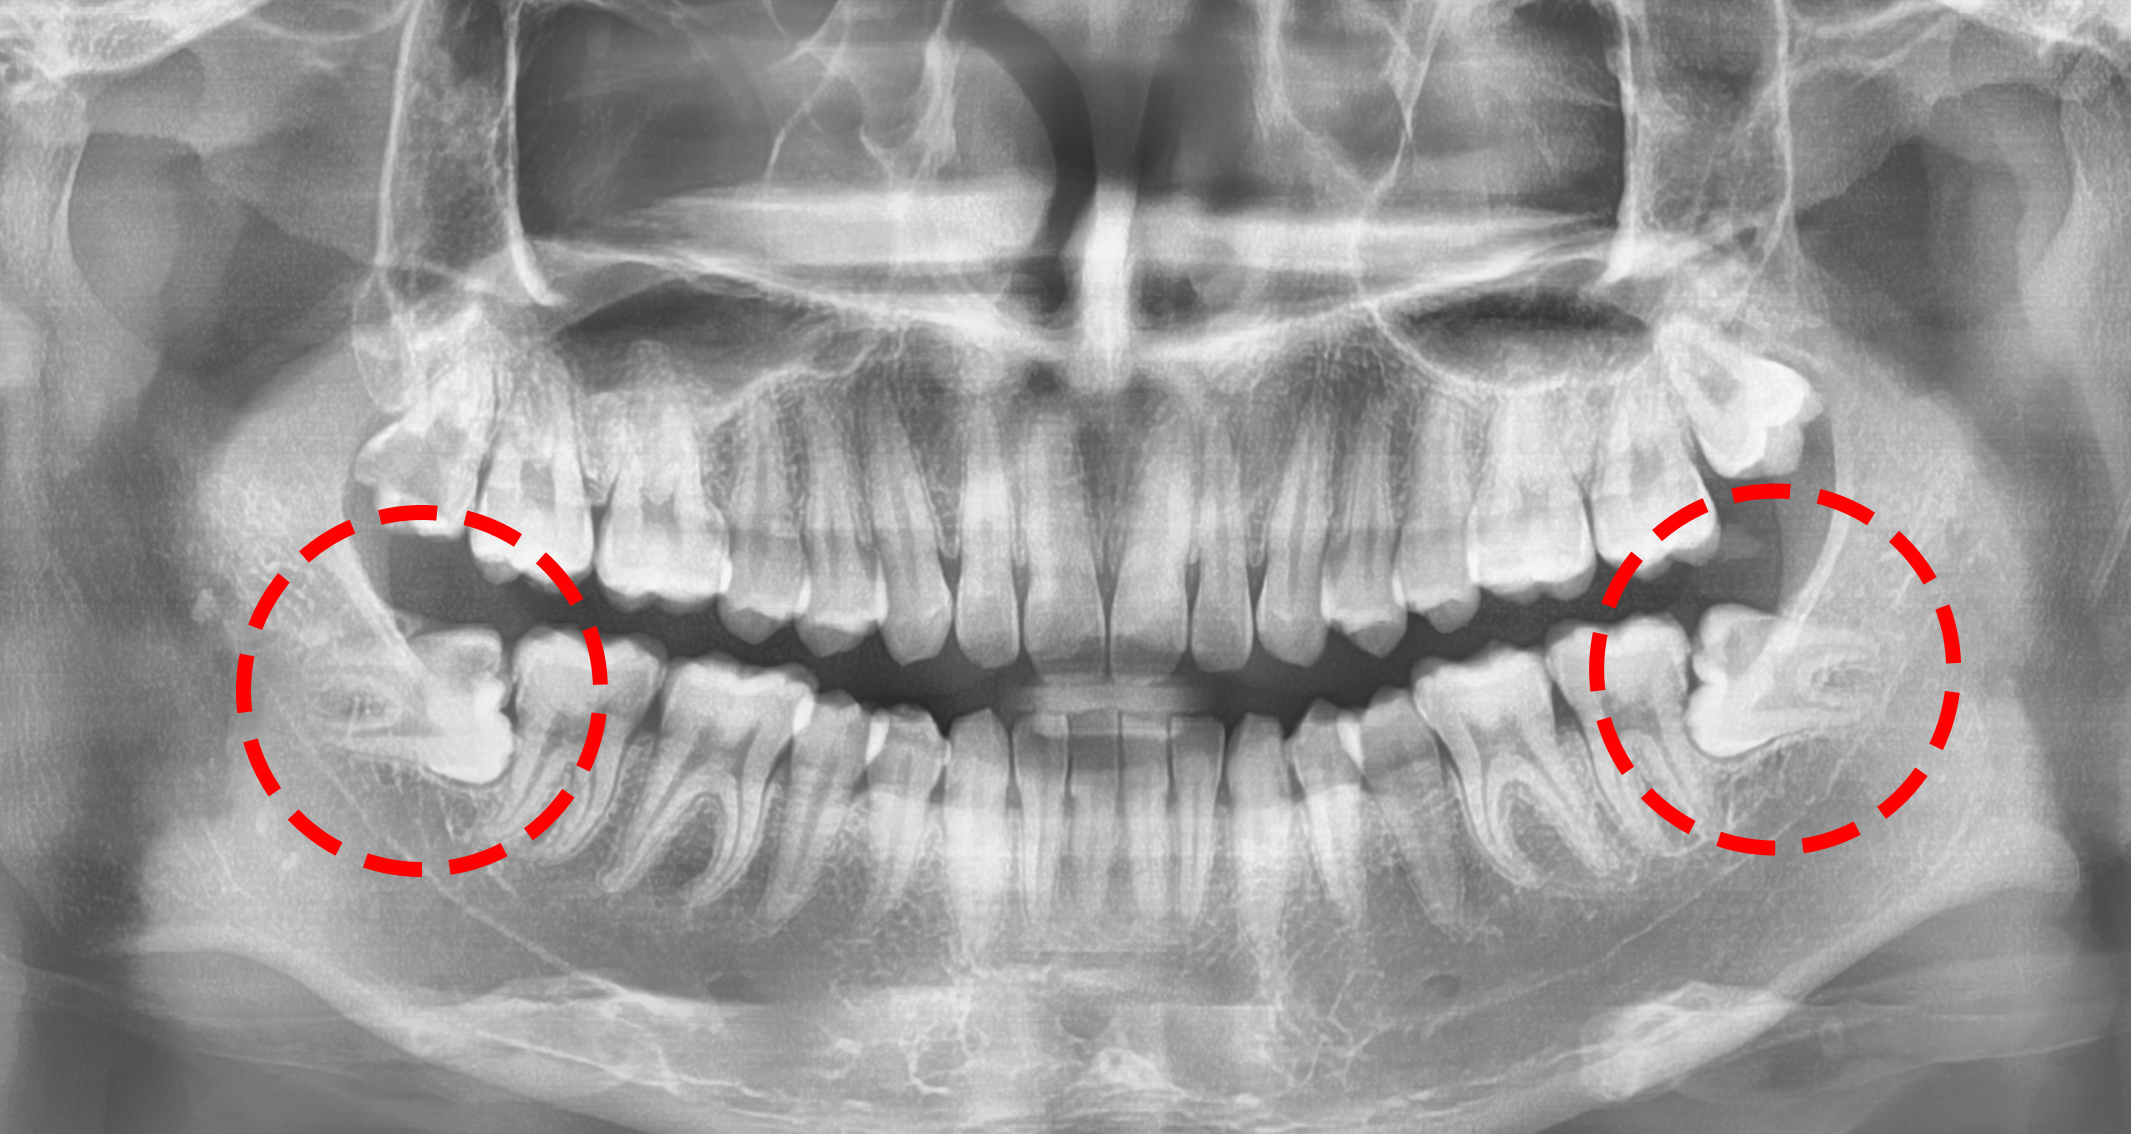

사진에서 볼 수 있듯이, 우측 바둑판 내를 보면

‘빨간색’ 으로 표기를 해둔 곳이

바로 신경관의 위치입니다.

“ 치아의 뿌리와 가까운 것을 볼 수 있죠? ”

게다가, 거리는 2.0mm 밖에 되지 않습니다.

즉, 신중히 발거를 하지 않으면

신경손상으로 이어질 수 있다는거..

신흥역치과 에서는 깔끔하게 다 뽑아드렸습니다.